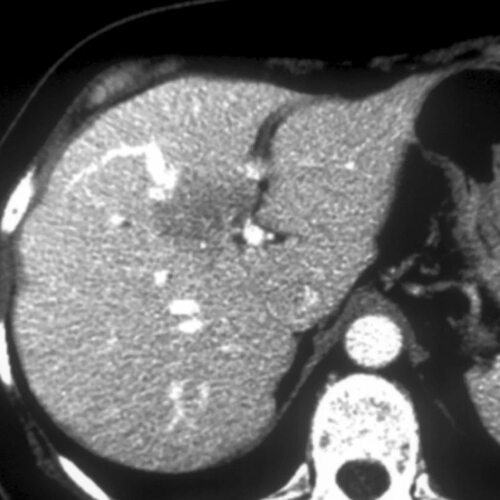

Жировая дистрофия печени кт

Воспалительная псевдоопухоль печени кт

Жировая дистрофия печени мрт

Фото жирового гепатоза на УЗИ

В данной статье представлены многочисленные фотографии, демонстрирующие характерные признаки жирового гепатоза на УЗИ. Вы сможете увидеть увеличение размеров печени, наличие жировых инфильтратов и другие изменения, связанные с этим заболеванием.